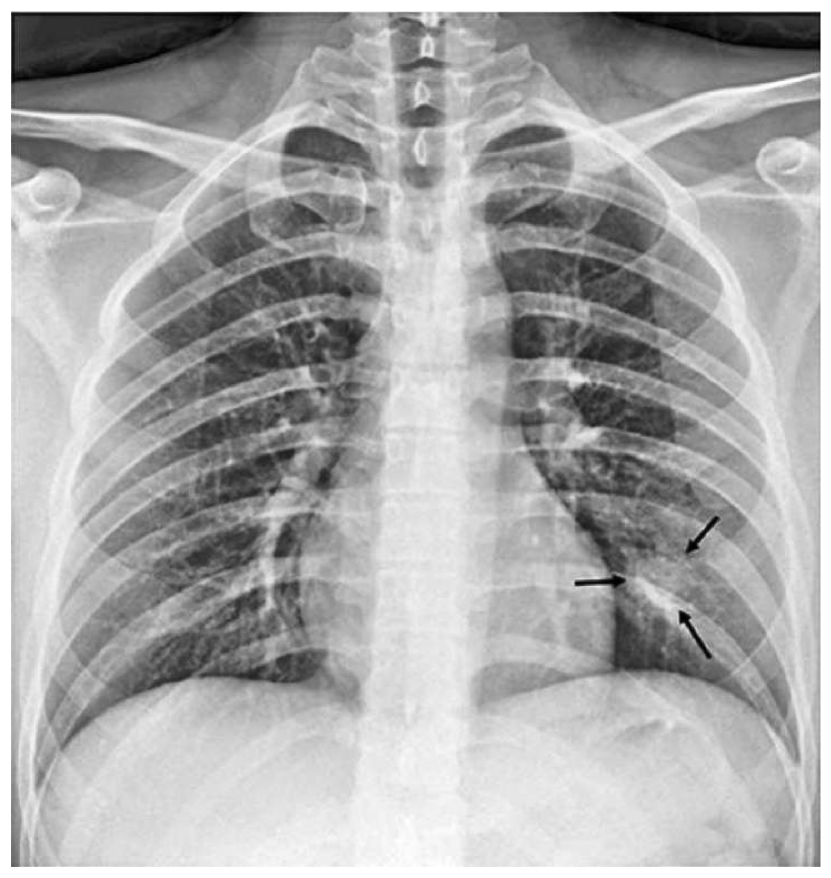

Appendix B More Grad-CAMs of the COVID-CXNet Model with Lung Segmentation Preprocessing

Refer to caption

Figure 21: Grad-CAMs from COVID-CXNet with lung segmentation module